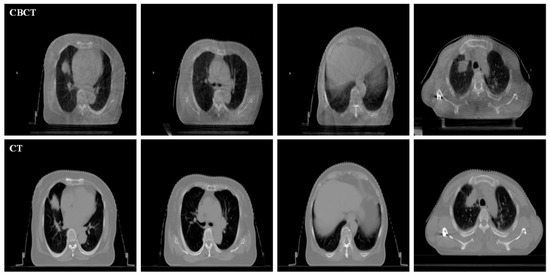

3.2. Subjective Comparison and Analysis

The visual comparison of different enhancement algorithms is shown in Figure 7, Figure 8, Figure 9 and Figure 10. Figure 7a is the source CBCT image, and Figure 7b is the image enhanced by MSR, which shows that the brightness of the source image is improved but with low contrast. Figure 7c,f,g show similar enhanced results with improved brightness but lacking in details. The DCP method improves the contrast of the source image, but does not enhance the details. As shown in Figure 7e, the CBF-based method shows good detail, but it still contains some noise. Compared with these methods, the proposed method shows better visual effects with higher contrast and richer detail, and the important regions are more significant.

Figure 7.

Enhanced results of pair 1. (a) Source CBCT images. (b) MSR. (c) MSRCR. (d) DCP. (e) CBF. (f) RRM. (g) SMIPC. (h) Ours.

Another three sets of experiments are shown in Figure 8, Figure 9 and Figure 10. As can be seen from the enlarged regions and the yellow arrows in Figure 8, it is difficult to directly observe the presence of skeletal information at this position from the enlarged region in Figure 8a. The enhancement results of the comparison methods also did not improve the visual contrast in this region, but the skeletal information can be clearly observed in our result, which means our results outperform the comparison algorithms in terms of detail, contrast, and visualization effect.

The same conclusion can also be obtained in Figure 9 and Figure 10. Especially in the enalrged region in Figure 10, our results provide a much clearer organizational structural and edge infromation, which is very helpful for disease diagnosis and treatment. Through comparison, it can be found that the rigidity informaiton in our results is more significant, the tissue edge in our results is clearer, and the contrast of the texture structure is also better than that of the comparison algorithms. The observation effect is greatly improved by our enhancement method, proving that our method can effectively enhance the CBCT images.